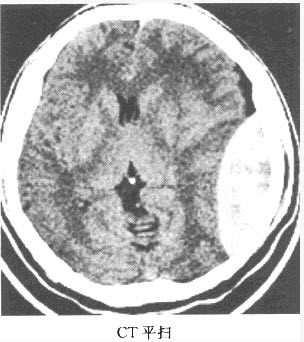

1、多项选择题 患者,女,80岁,被人发现昏迷,大小便失禁10小时入院。体格检查:血压180/100mmHg,心率约110次/分,有房颤,体温37℃,浅昏迷,右侧肢体未见自主活动,肌力增高,Babinski征阳性,GCS=E2+V1+M3=6分,有风湿性心脏病和房颤病史,既往超声检查有二尖瓣赘生物。 你的诊断依据是哪些()

B.CT示脑实质内大面积均匀低密度区

C.脑实质内见类圆形密度增高影,边缘见大面积低密度区

F.CT示脑实质内低密度区不强化

患者检查图像如下,你考虑何种疾病()